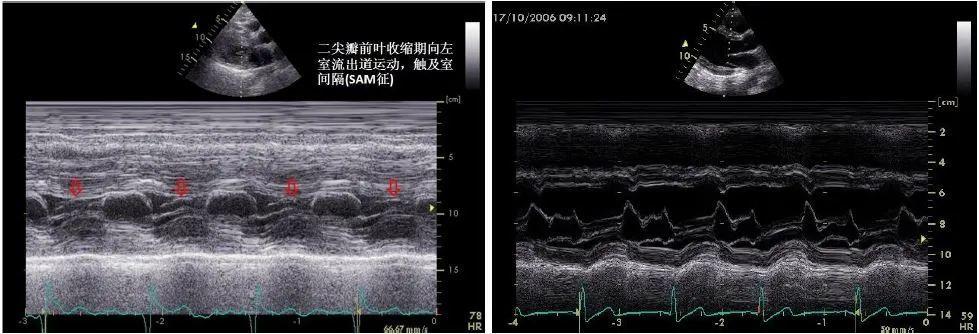

sam征超声表现,sam征

超声心动图 sam征小知识

sam征

二尖瓣sam征示意图

二尖瓣sam征图

sam征超声示意图

sam征超声心动图

sam现象超声图片

sam征阳性超声图片

二尖瓣sam征M型示意图